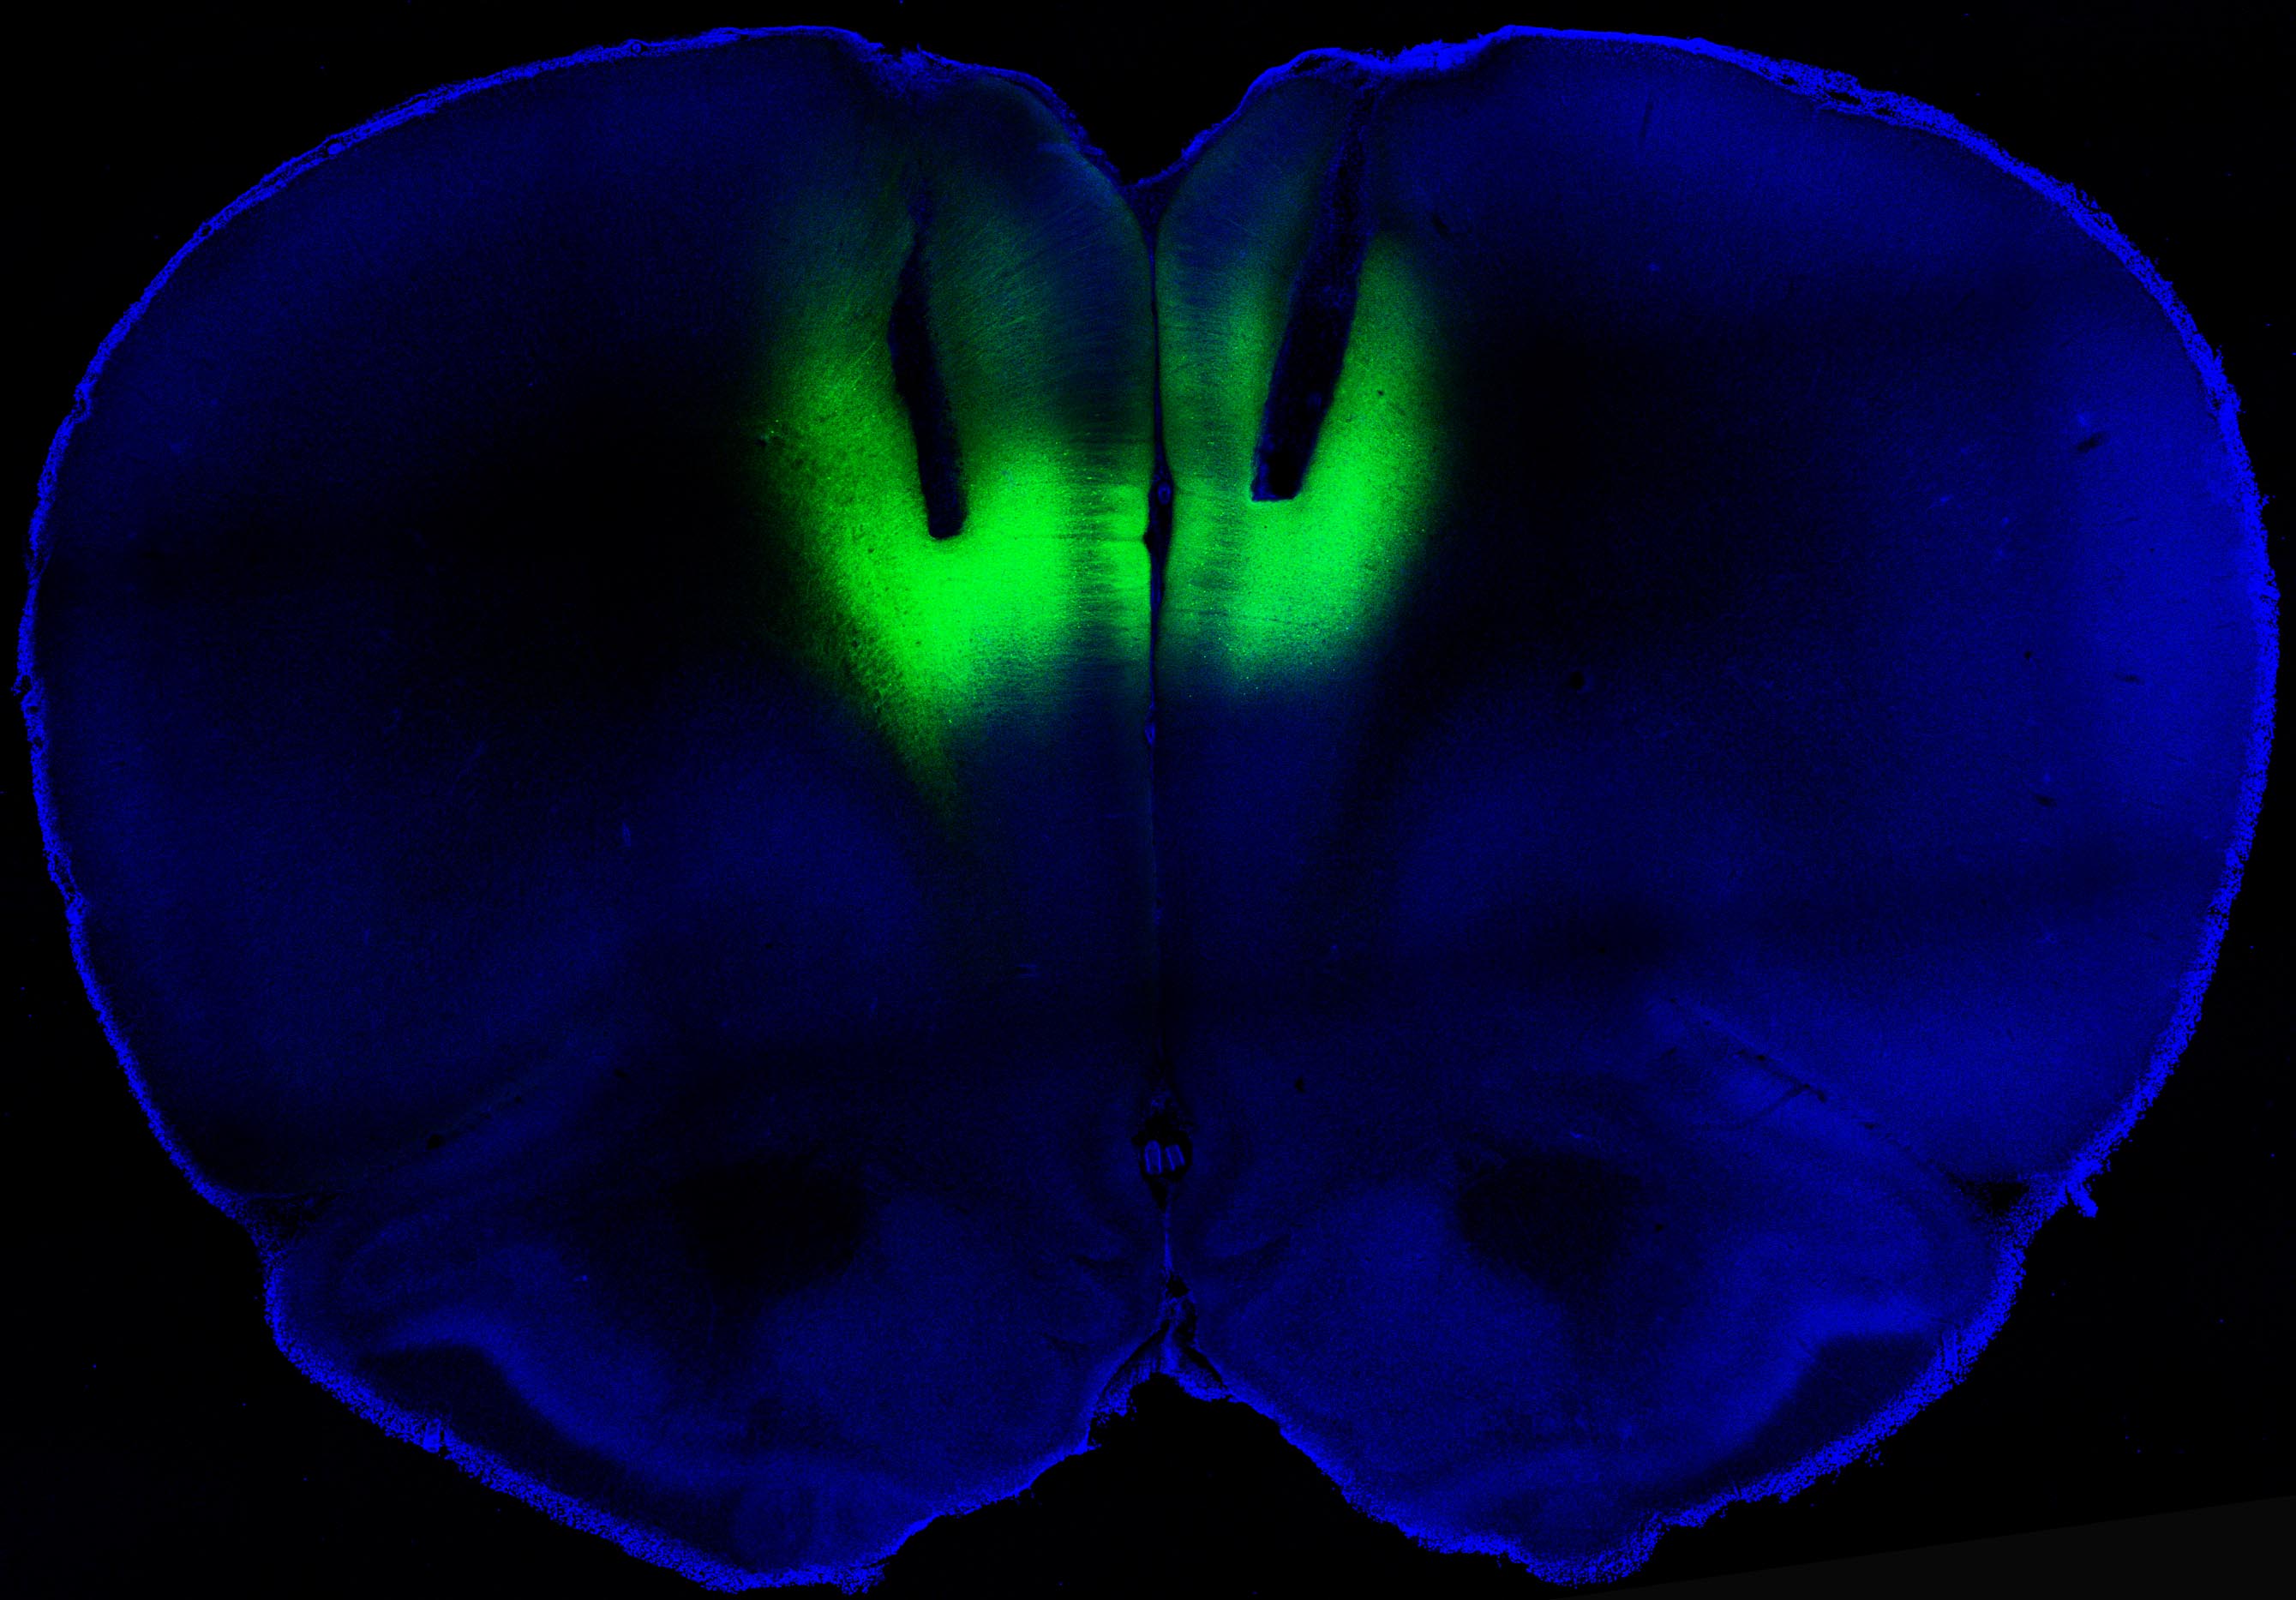

To test whether altering the activity in this brain region could impact addiction, Chen and his colleagues employed a technique called optogenetics to shut the activity on and off using a laser.

First they took light-sensitive proteins called rhodopsins and used genetic engineering to insert them into neurons in the rat’s prefrontal cortex. Activating this region with a laser tuned to the rhodopsins turned the nerve cells on and off.